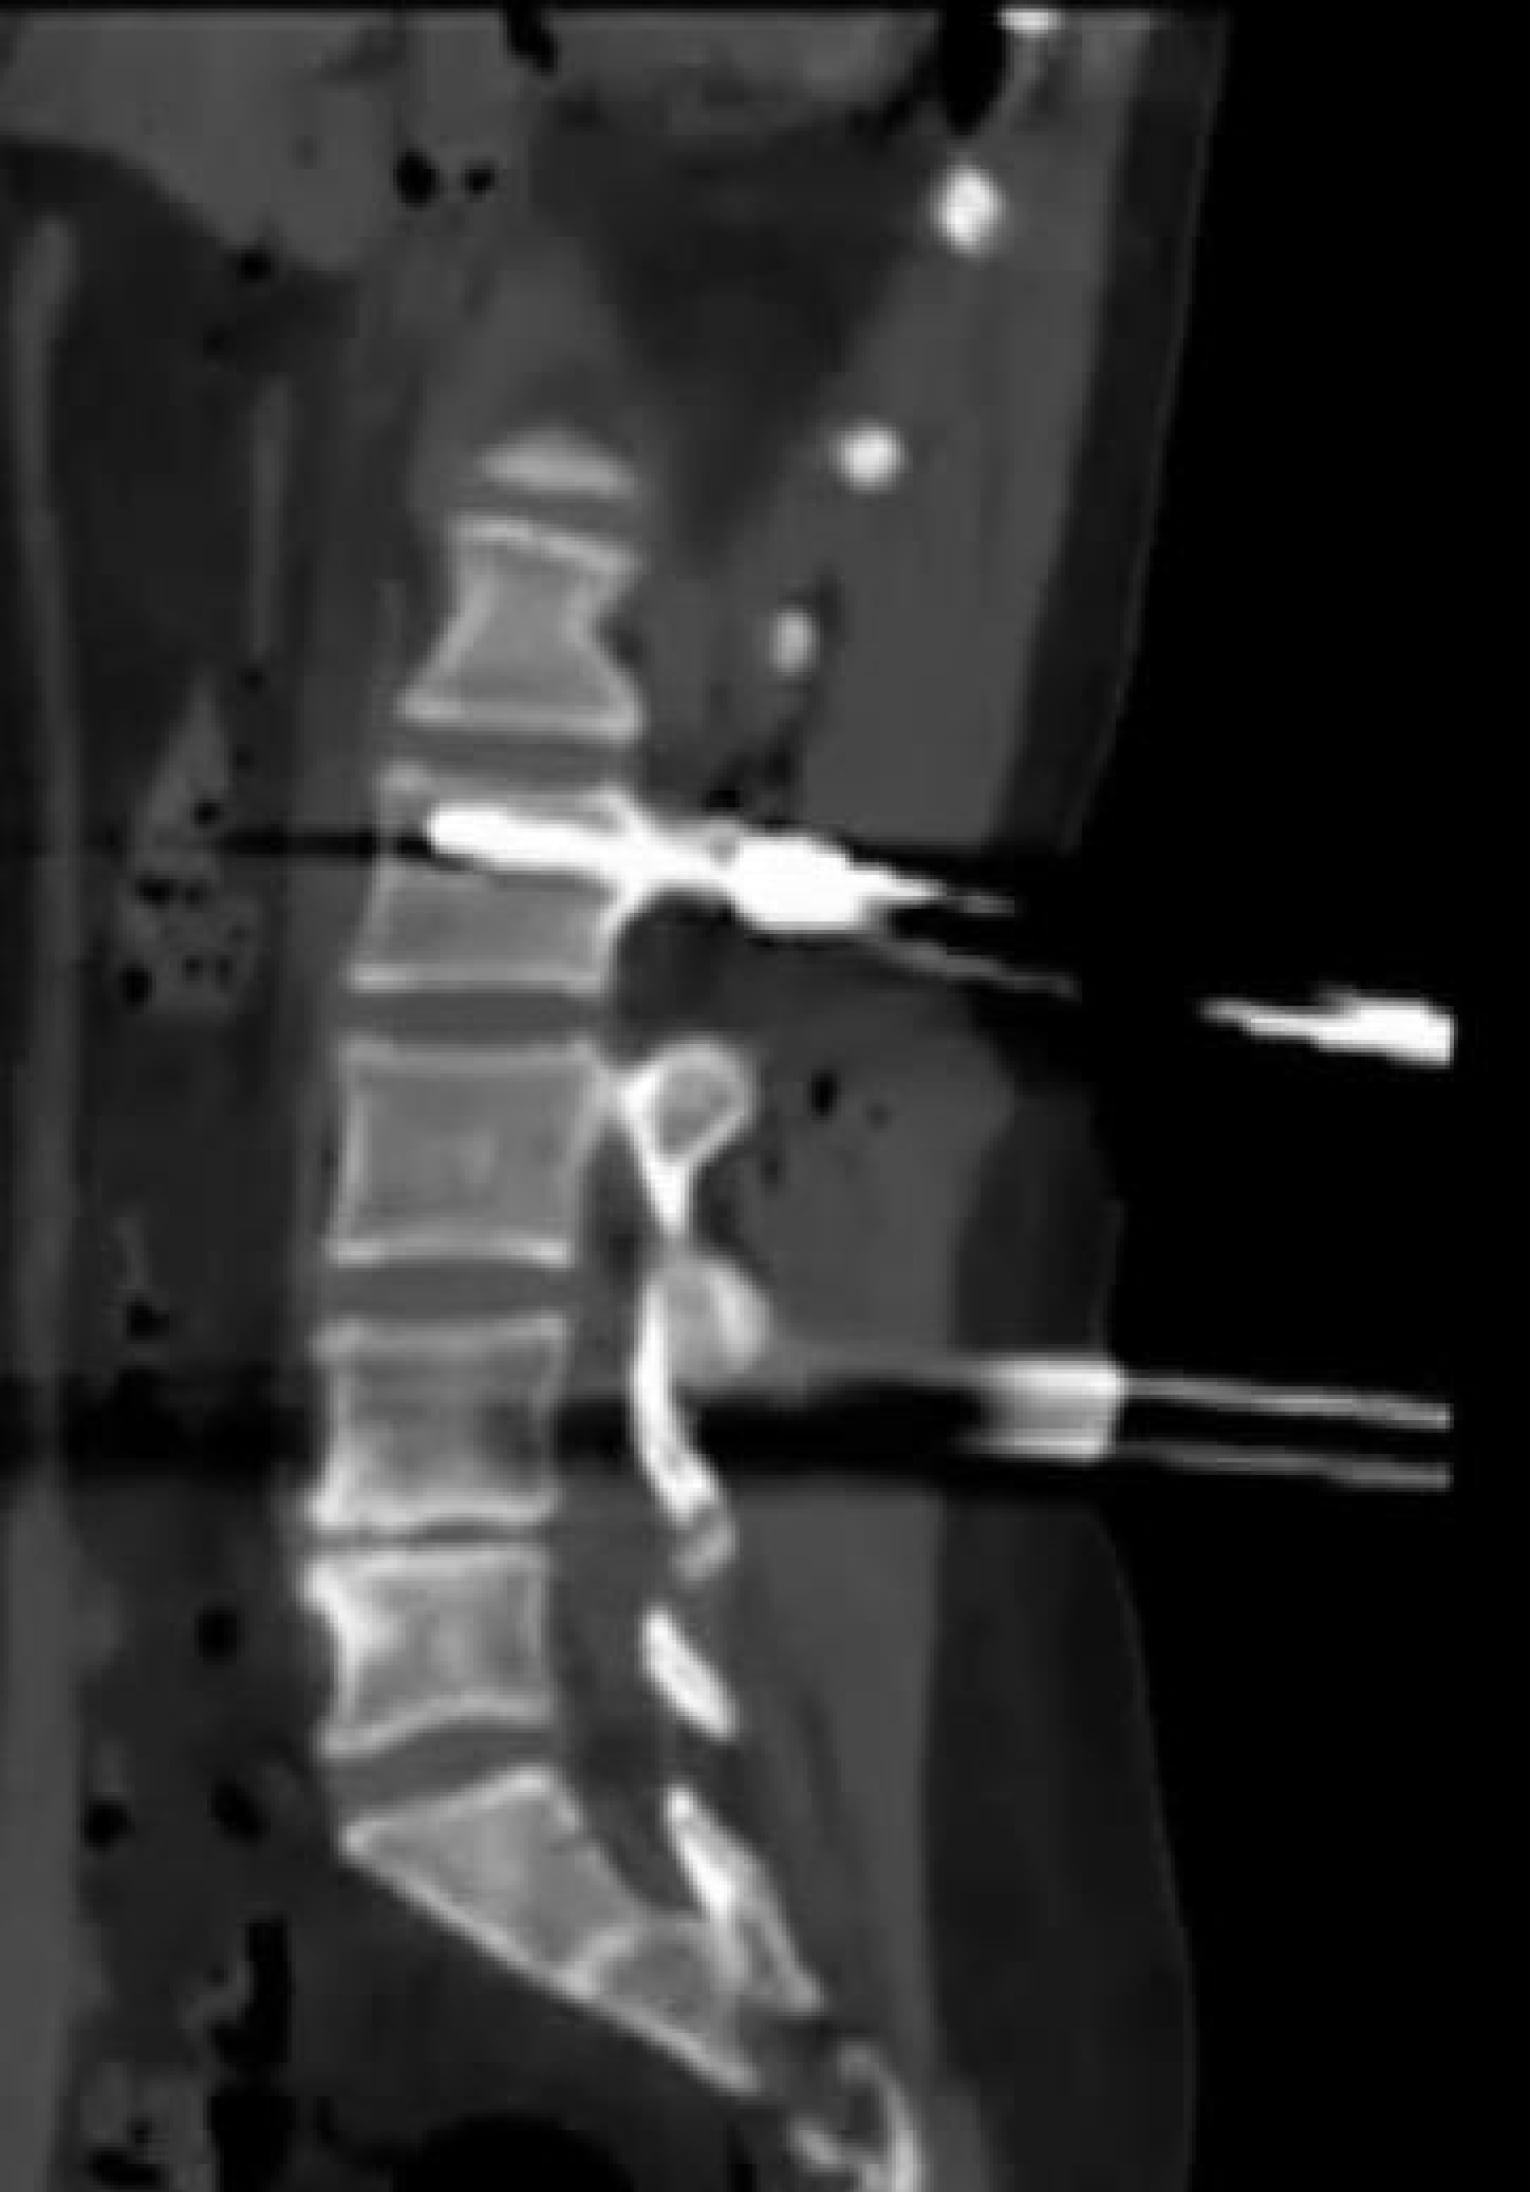

Neueste Technologie in der intraoperativen Bildgebung

Diese Methode ist insbesondere bei komplexen Operationen von großem Vorteil, da sie eine genauere Überwachung des chirurgischen Eingriffs ermöglicht. Zudem können im Verlauf der Operation wichtige Informationen und Daten erhoben werden, die für die weitere Behandlung von großer Bedeutung sind.